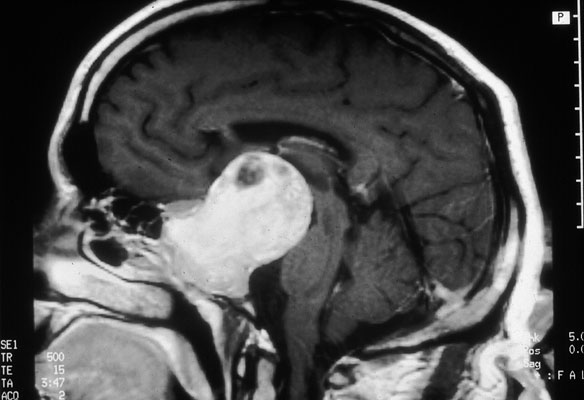

Macroadenoma of pituitary, MRI, saggital view

MRI scan of macroadenoma: sagittal view.